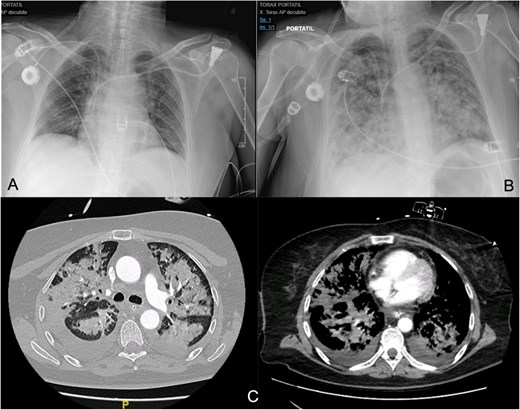

Around 36 h post-surgery, the patient developed sudden acute respiratory failure requiring escalating doses of norepinephrine. Imaging studies revealed bilateral interstitial infiltrates consistent with a differential diagnosis of ARDS or acute pulmonary oedema (APE) (Fig. 1). Despite broad-spectrum antibiotics and respiratory support, progressive hemodynamic deterioration ensued, prompting surgical re-exploration. Laparotomy revealed patchy intestinal ischemia likely secondary to multiorgan failure (MOF), culminating in the patient’s death. Autopsy findings revealed systemic endothelial damage with calcium deposition resembling ischemia–reperfusion injury without evidence of sepsis.

(A, B) Differences between the chest X-ray in the immediate postoperative period and at 36 h after the onset of respiratory failure. (C) The chest CT confirms pulmonary exudates compatible with ARDS (acute respiratory distress syndrome).